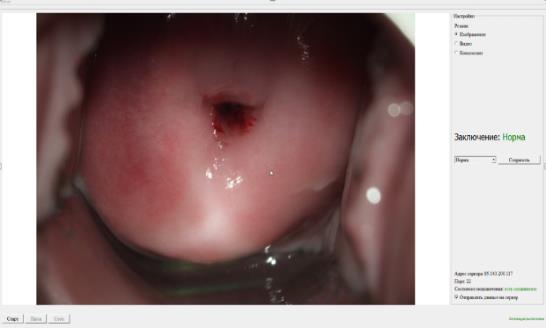

Разработано медицинское изделие «Программа ЭВМ на основе искусственного интеллекта для повышения точности диагностики рака шейки матки». Выполнена валидация конечного программного продукта (Нейросетевой алгоритм), созданного для ранней диагностики рака шейки матки в клинических условиях. Проведен сбор параметров о чувствительности (81%) и специфичности (86%), площадь под кривой (89%) метода, отладка, повторные повторяющиеся тренировки нейронной сети с учетом ранее распознанных ошибочных распознаваний. С целью регистрации разработанной программы ЭВМ как медицинского изделия, успешно пройдены технические и клинические испытания.